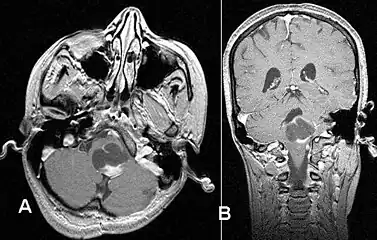

Stereotactic MRI brain scan showing a recurrent postoperative brain stem cystic pilocytic astrocytoma. -

Pilocytic astrocytoma in the hypothalamic region. -

Axial non-contrast CT in a nine-year-old girl showing a slightly hypodense mass in the tectum of the brainstem, compressing the aqueduct of Sylvius and causing obstructive hydrocephalus -

Sagittal T1-weighted MRI showing a well-circumscribed hypointense mass in the tectum (presumably a tectal plate glioma). These lesions are a distinct subset of pilocytic astrocytoma which present with hydrocephalus typically in 6 to 10 year-olds and are rarely progressive lesions. When imaging is characteristic, a biopsy is usually not performed because of the risks to adjacent structures, often shunting to relieve intracranial pressure is the only treatment required. -

T1-weighted coronal MRI image postcontrast showing heterogeneous contrast enhancement within the presumed tectal plate glioma

Usually – depending on the interview of the patient and after a clinical exam which includes a neurological exam and an ophthalmological exam – a CT scan and/or an MRI scan will be performed to confirm the presence of a tumor. They are usually easily distinguishable from normal brain structures using these imaging techniques. A special dye may be injected into a vein before these scans to provide contrast and make tumors easier to identify. Pilocytic astrocytomas are typically clearly visible on such scans, but it is often difficult to say based on imaging alone what type of tumor is present.